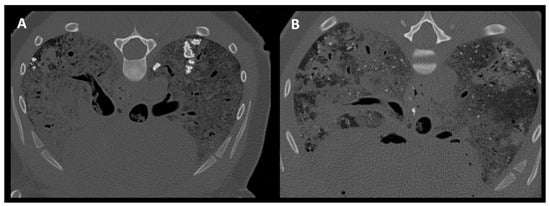

3.4. Pulmonary Parenchymal Attenuation Changes